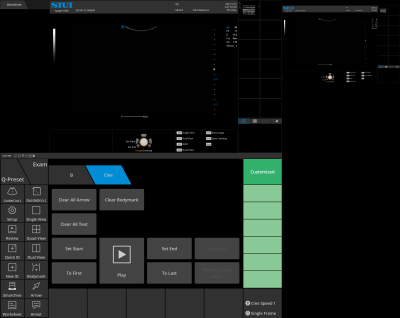

Q-preset

Without entering setup interface, user-defined parameters can be saved quickly with one click.